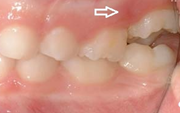

Esimeste molaaride (purihammaste) lõikumine

Esimeste molaaride (purihammaste) lõikumine. 1. molaaride ektoopilise lõikumise jälgimine. Ülemised ja alumised esimesed purihambad e. molaarid lõikuvad orienteeruvalt6-7-aastaselt piimahammaste rea lõppu. Enamasti lõikuvad samanimelised jäävhambad paaridena. Normaalne lõikumise Loe edasi »